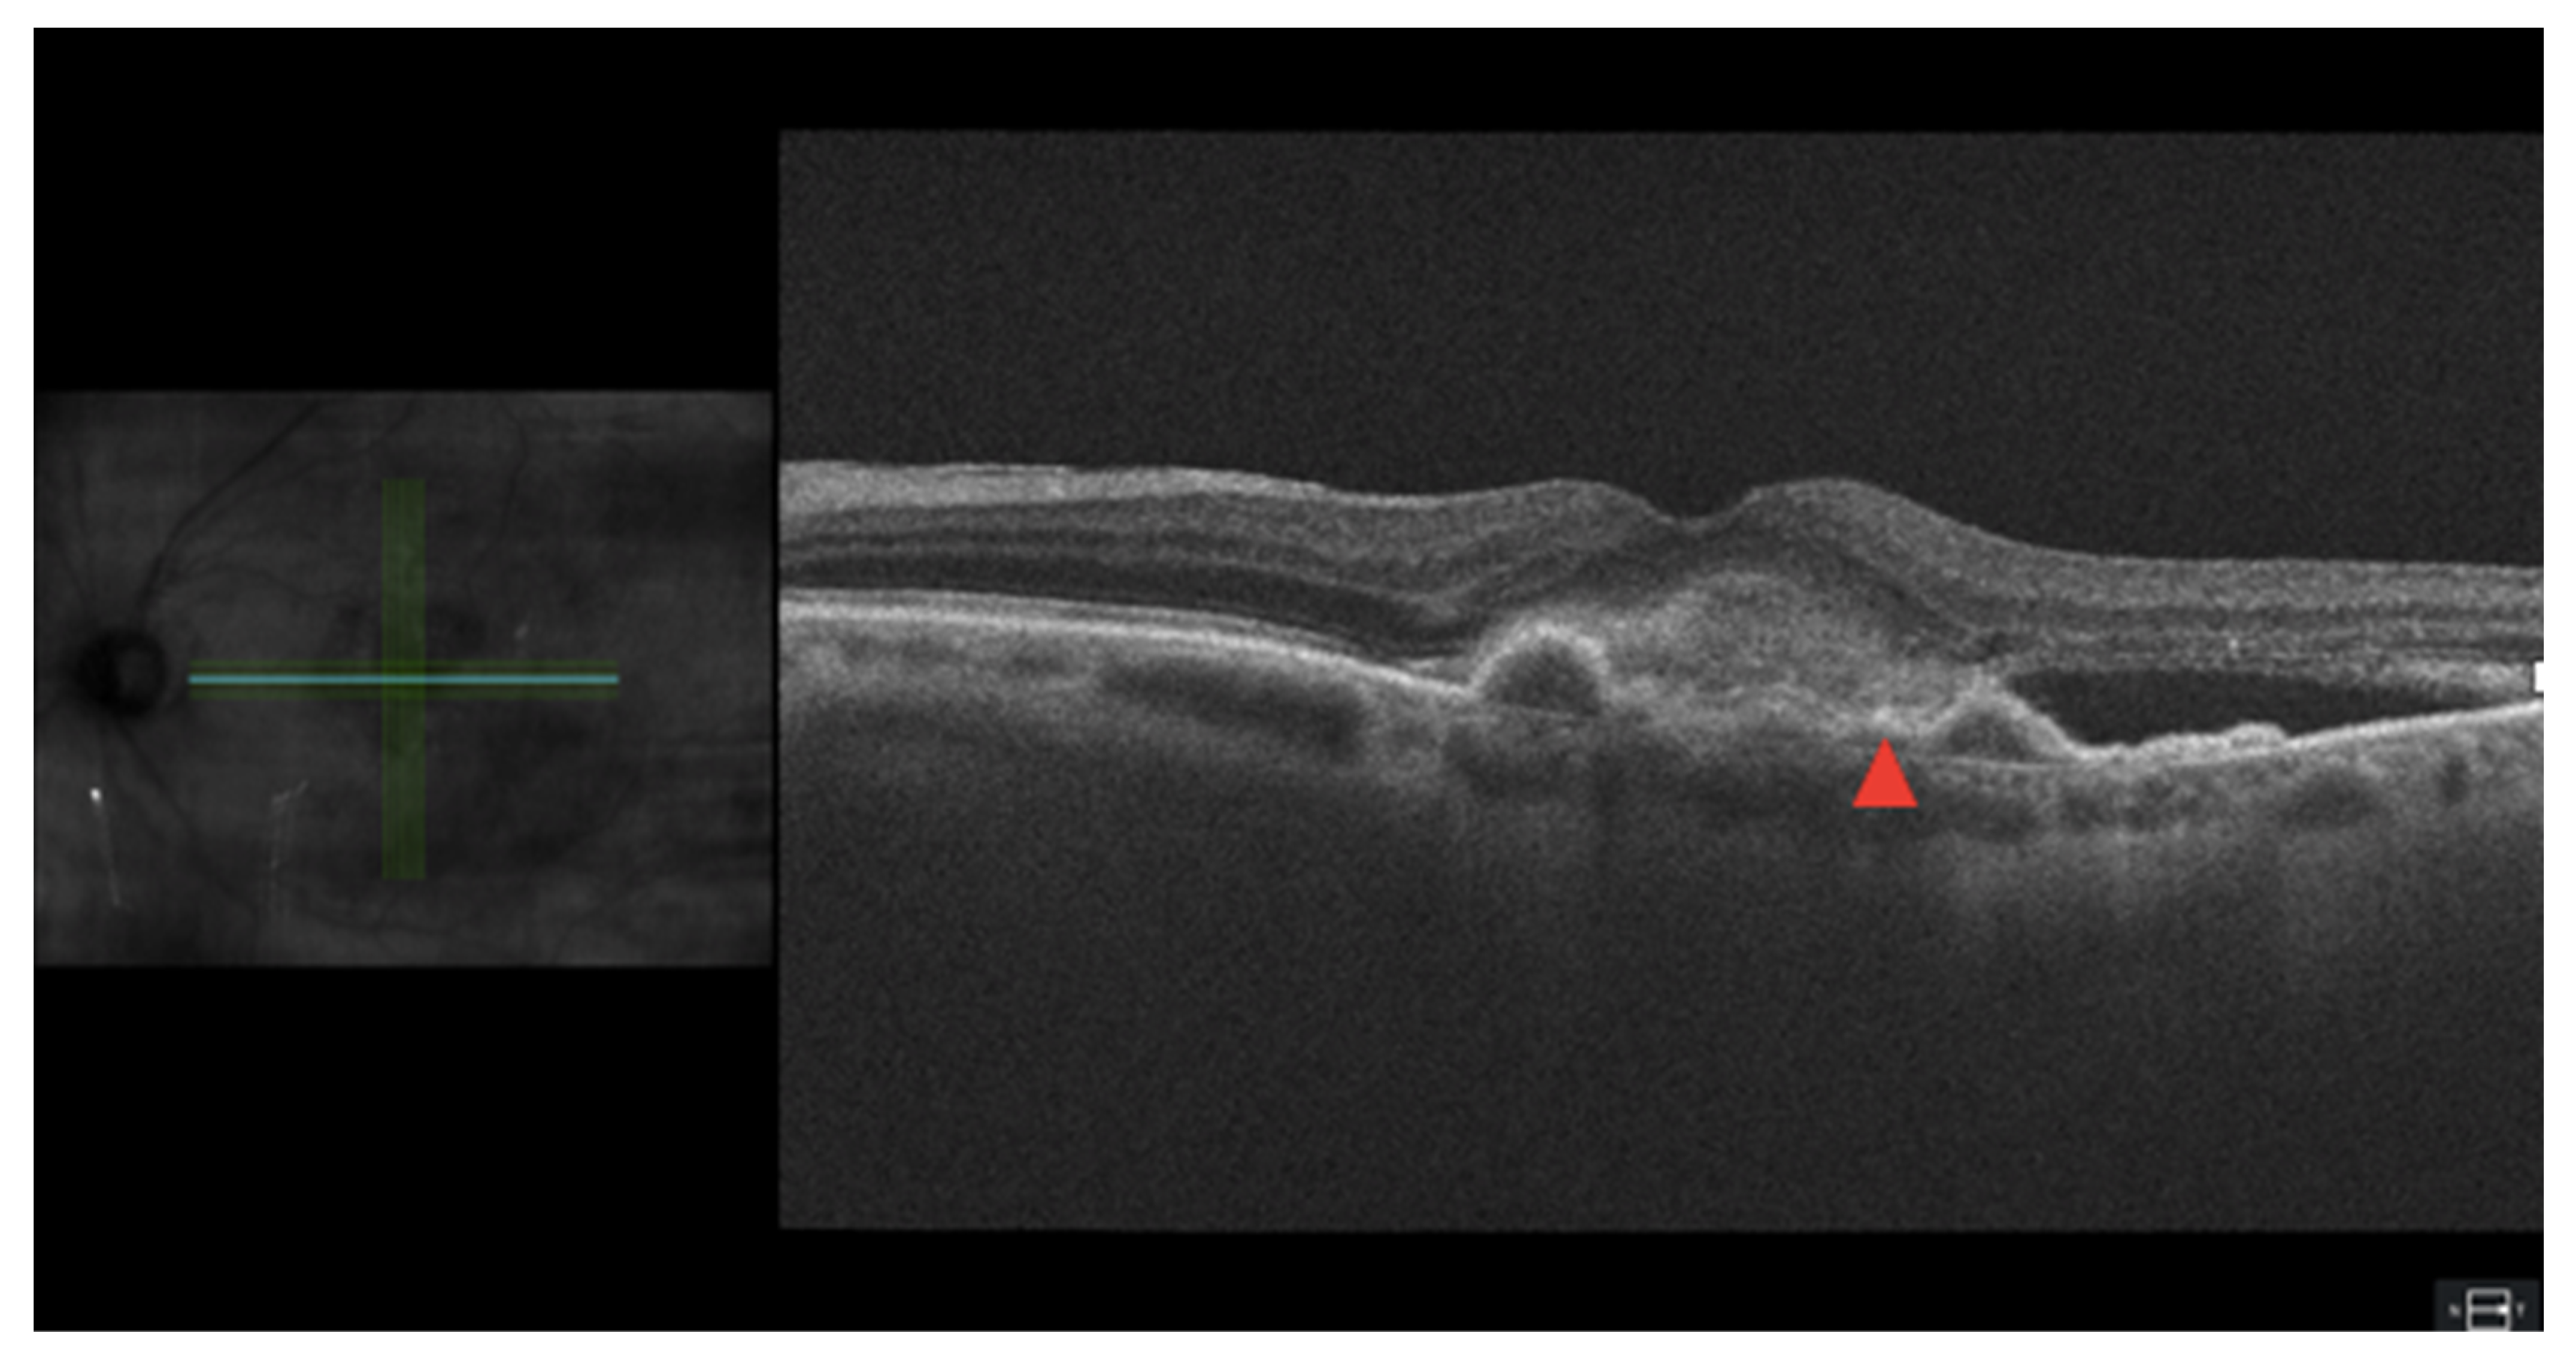

3.4. Hyper-Reflective Material

Figure 3.

SRHM and PED in age-related macular degeneration on optical coherence tomography. Green and blue scan lines spanning location of en-face scross-section. Area of hyperreflectivity marked with a red arrow.

Some SHRM descriptors that could provide clinical utility are size, configuration, reflectivity, and structural integrity of certain retinal layers. Even though the shape of SHRMs is not associated with a difference in the BCVA, the size of SHRMs in both height and width is highly correlated with a worse BCVA, with increased width being the strongest predictor. Patients can compensate better with narrower SHRM lesions and are therefore less harmful than wider lesions, both having multiple lines of hyperreflectivity and increased reflectivity in SHRM portend a poorer prognosis [40]. SHRM also increases the risk of scar formation in eyes with nAMD, which leads to further retinal disruption and decreased visual acuity [41].